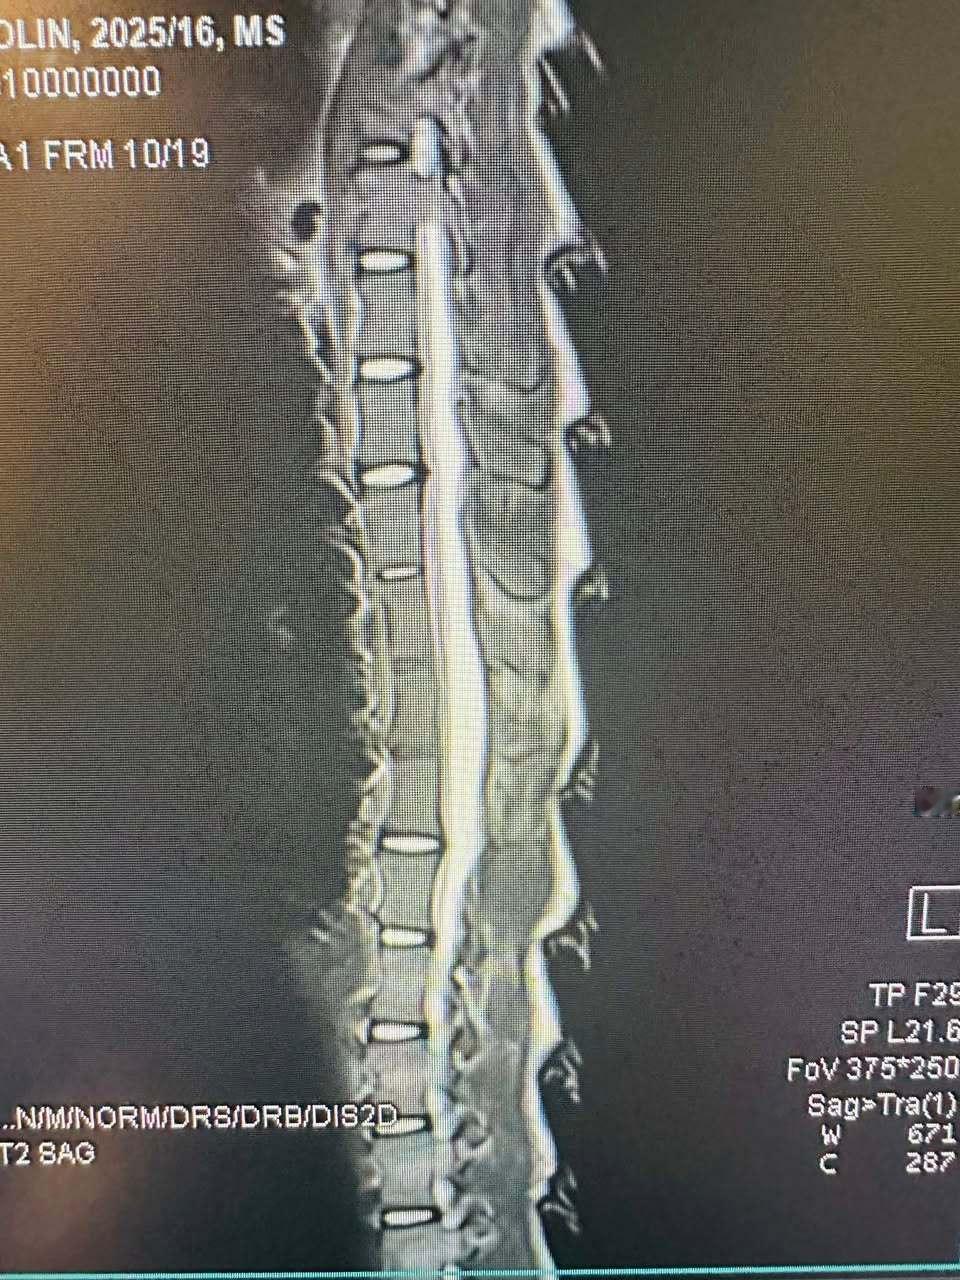

这只叫做Heritage的雌性穿山甲,在南非被从非法交易中解救出来的时候,有着严重的脊柱感染情况。当时大家都不太乐观,因为首次在救助的穿山甲身上发现这种病例。但是经过野生救护人员的悉心救助和护理,60天的高强度治疗后,再次做核磁共振检查时候发现她已经完全康复啦!!感谢所有付出努力的人们~也感谢高度配合的Heritage自己~努力获得了新生图1看到那个小脑袋,原谅我真的笑了半天【脸书:Umoya Khulula Wildlife Centre】